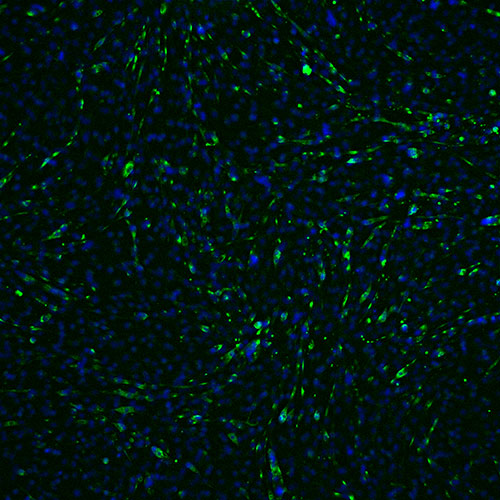

Technical excellence in our preclinical CRO Services

- Aging Model for example

Health Muscle Cells

Blue: nucleus

Green: myotube

Senescent Muscle Cells

Senescent and Toxin-damaged Muscle Cells